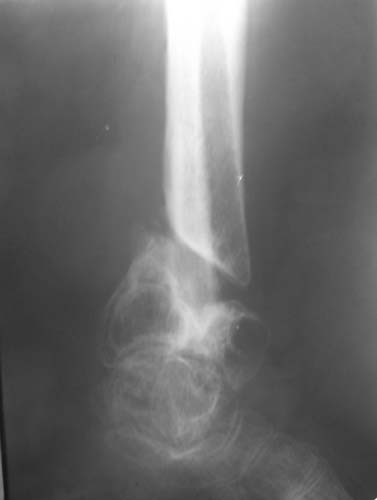

Женщина, 62 года. Травма 2 года назад в результате ДТП. Находится на лечении с 30.10.06 года с диагнозом: Несросшийся перелом дистальной трети правой большеберцовой кости с угловыми деформациями дистального отдела конечности, дефектом костной ткани.

Рубцовой деформацией мягких тканей медиальной поверхности дистальной трети голени. Нейротрофические нарушения. Посттравматический остеопороз. Дегенеративно-дистрофический остеоартроз правого голеностопного сустава.Сопутствующая патология.: ЖКБ, хронический калькулезный холецистит в стадии ремиссии. МКБ, хронический пиелонефрит в стадии ремиссии.Ожирение 3 ст. Посттромбофлебитический синдром нижних конечностей, ХВН 2 ст. Посттравматическая нейропатия левого малоберцового нерва с парезом левой стопы. Какие предложения по тактике лечения? Заранее благодарю!

Голеностопный сустав тут, видимо, потерян. Так что надо думать только про стабилизацию. Какие из существующих вариантов артродеза доступны, и какой из доступных оптимален? Антон, есть ли смысл обсуждать варианты с закрытым штифтованием, доступно оно? Если да, то Алексей Семенистый предлагает вполне жизнеспособный план (хотя можно и антгерадно сделать). Если нет, то надо что-то придумывать с аппаратом. Наверно, латеральным доступом кпереди от fibula с ее пересечением открыться, и что-то костно-пластическое делать.